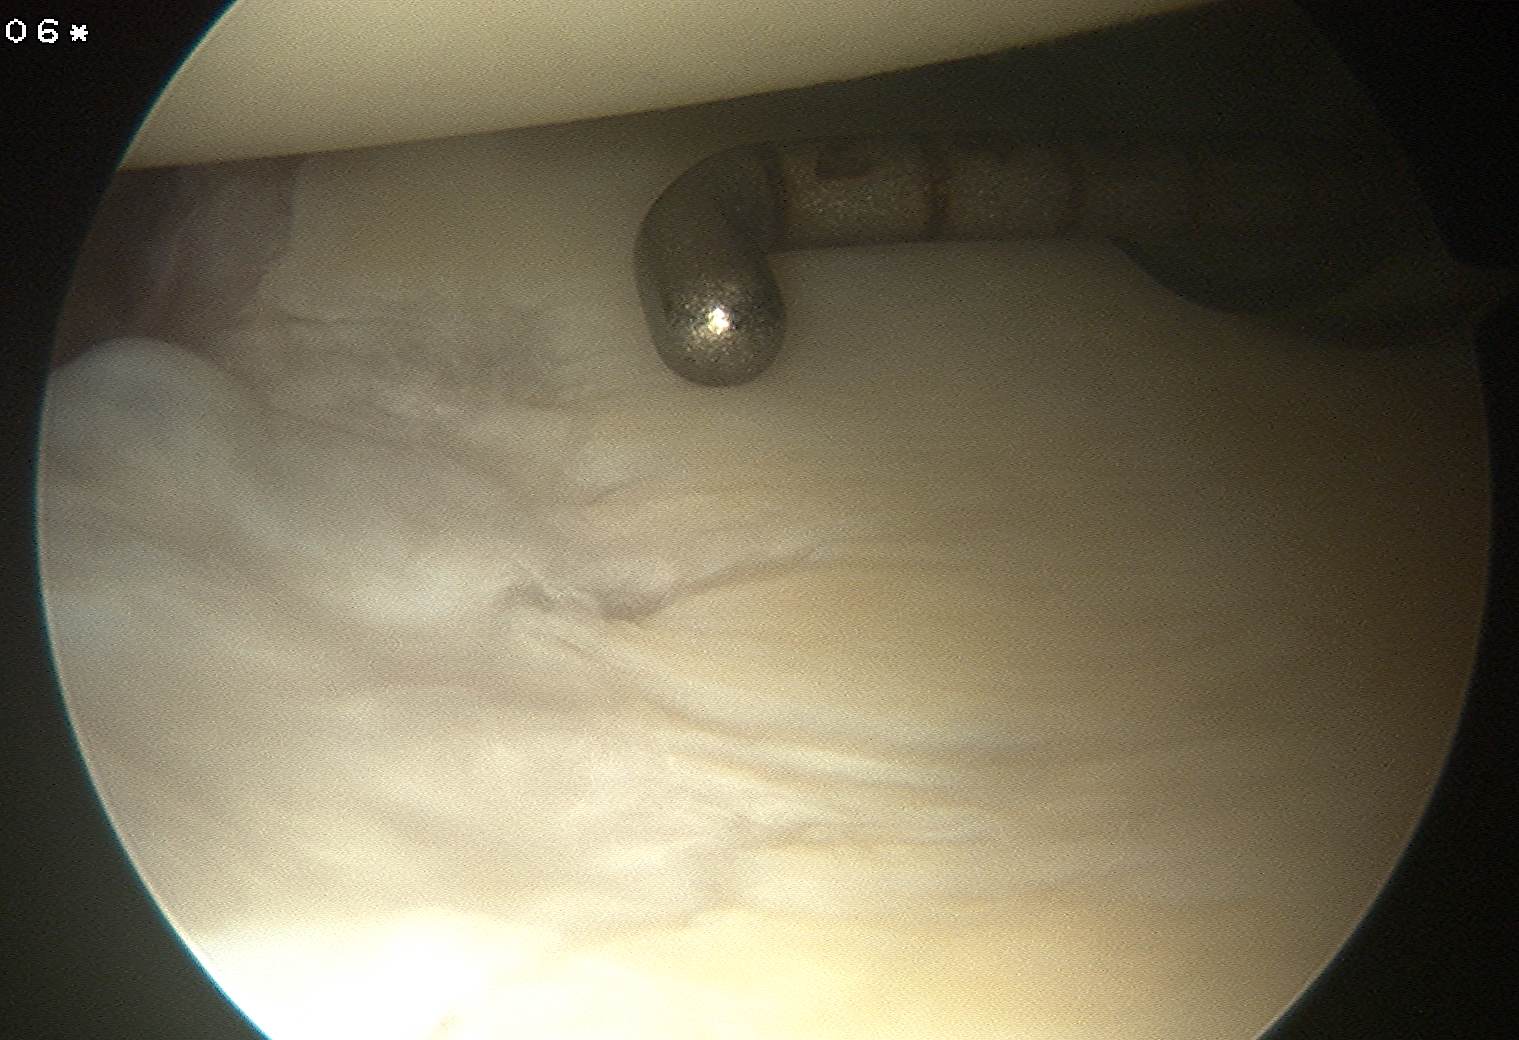

Insert anchors

Inferior anchor at 5.30 o'clock

- curved anchor guide / trans-subscapularis

- on rim of glenoid

Other anchors typically at 3 and 4 o'clock